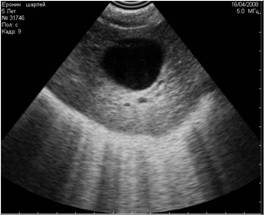

Рис1. Помехи, вызванные включённым рядом с аппаратом УЗИ сотовым телефоном. Во избежание этого лучше просить владельца выключать сотовый телефон при проведении ультразвукового исследования. |

Рис2. Помехи, вызванные работающими электроприборами, включёнными в сеть рядом с аппаратом УЗИ. |